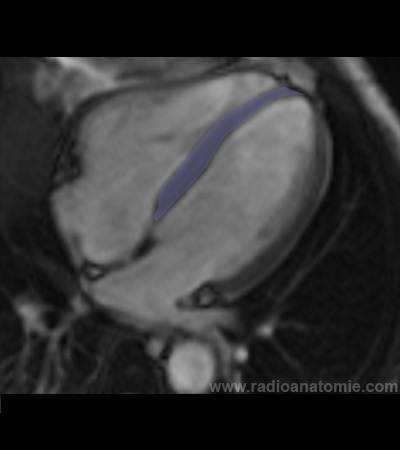

Radioanatomie et plans de coupe en IRM cardiaque

Septum interventriculaire